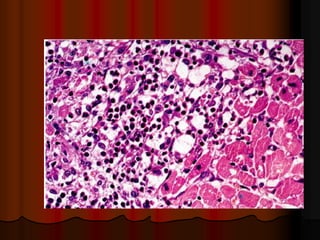

Эндомиокардиальная биопсия

В настоящее время считается, что

диагноз "миокардит" может быть

подтвержден только данными

эндомиокардиальной биопсии, которая,

однако, дает много

ложноотрицательных и сомнительных

результатов. При оценке результатов

биопсии, как правило, используются

Далласские диагностические критерии

 5. «Золотым стандартом» диагностики

миокардитов в настоящее время

является прижизненная